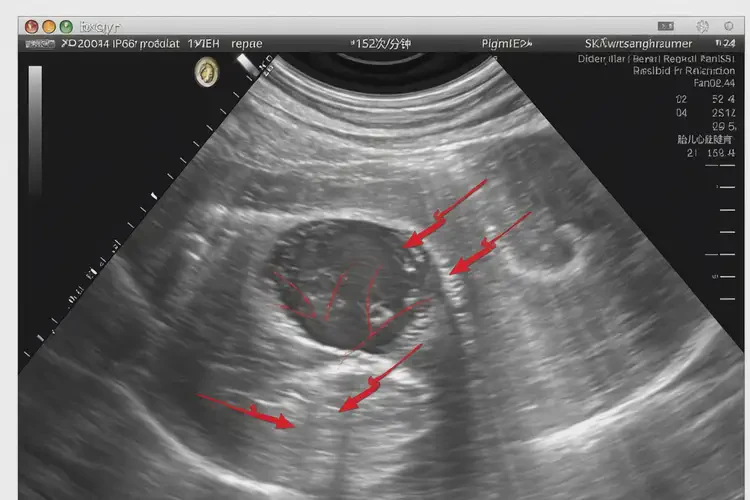

152次/分鐘

懷孕26周時(shí),胎心152次/分鐘屬于正常范圍。胎心率是指胎兒心臟每分鐘跳動(dòng)的次數(shù),通常在120-160次/分鐘之間被認(rèn)為是正常的。

懷孕26周胎心152正常嗎(圖1)